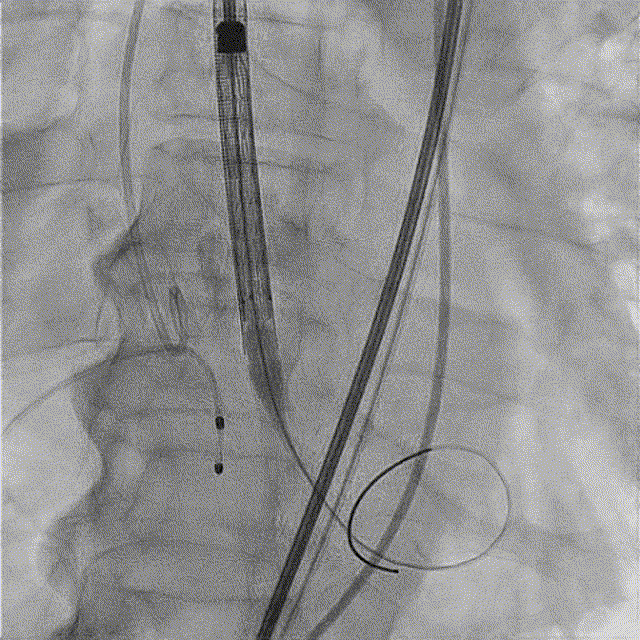

TaurusNXT植入过程

全麻后超声引导下建立入路,左侧股动脉置入TaurusNavi 20F血管鞘。跨瓣后左室放置Lunderquist导丝,使用TaurusAtlas 20mm球囊预扩,球囊无明显位移,有轻微腰征、无漏。输送系统预备同侧Snare从右股动脉送入,安全顺利通过主动脉弓。瓣膜在双窦展开位约瓣上2mm位初始定位释放,工作位造影多角度评估后予以释放(一次定位释放,未采用多次回收功能)。超声下显示瓣膜偏椭圆,之后使用TaurusAtlas 22mm球囊后扩,支架形态改善明显,导管测压由术前的70mmHg即刻下降至1mmHg,术后即刻超声心动图评估显示瓣膜位置良好,微量瓣周漏,血流动力学指标理想。

术中影像

主动脉根部造影

球囊预扩

预备Snare跨瓣

瓣膜初始定位

工作位造影(双窦展开位)

完全释放

球囊后扩

最终造影